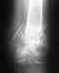

Мой отец 1958 г.р. 13.09.2014 г. при падении получил травму позвоночника. Перелом C3-C4.

С 13.09.2014 г. по 14.10.2014 г. находился на лечении в травматологическом отделении. В настоящее время в неврологическом отделении ЦРБ. Консультируете ли он-лайн? Возможно ли прохождение реабилитации в Вашем центре? Что для этого необходимо?